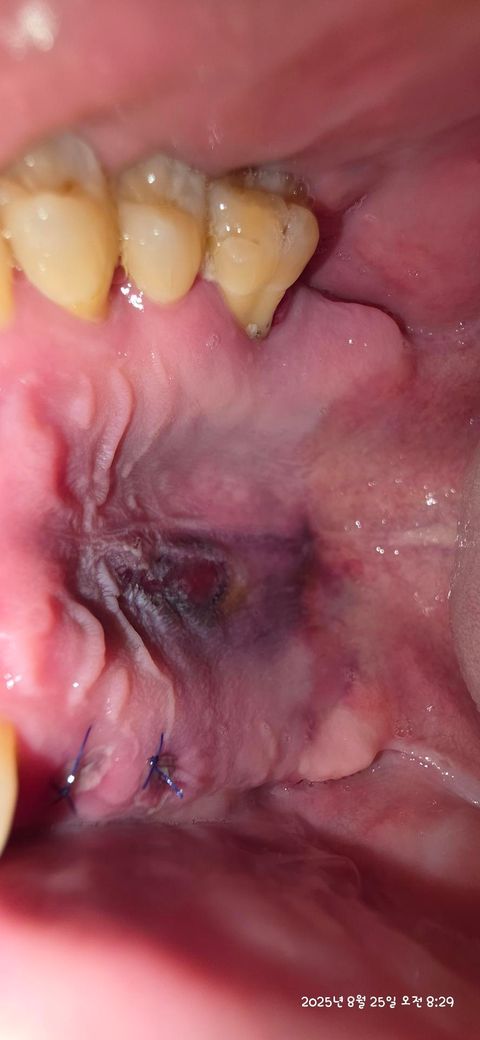

인플란트 시술후 입천장 멍자국 어떤가요?

인플란트 식립하고와서 보니 입천장이 저렇게 되어있습니다. 이전에도 이랬던 것 같은데 이러는 이유가 뭘까요? 지금은 입천장 까진 것 과 비슷한 통증느껴 집니다

잇몸 내에 출혈이 생겨서 그렇게 보일 수 있으며 보통 일주일정도 이내에는 정상적으로 회복됩니다

임플란트 식립시 입천장이 눌려서 생긴 멍자국같습니다 시야 확보를 위해서 당기거나 눌리면 피가 뭉쳐서 그럴수 있습니다.

임플란트 수술을 하게 되면 출혈이 되어 내부에 사진처럼 멍이 들수 있습니다. 멍은 2~3주정도 지나면 줄어들게 되며 통증이 있다면 처방된 진통제를 복용하는것이 좋습니다.